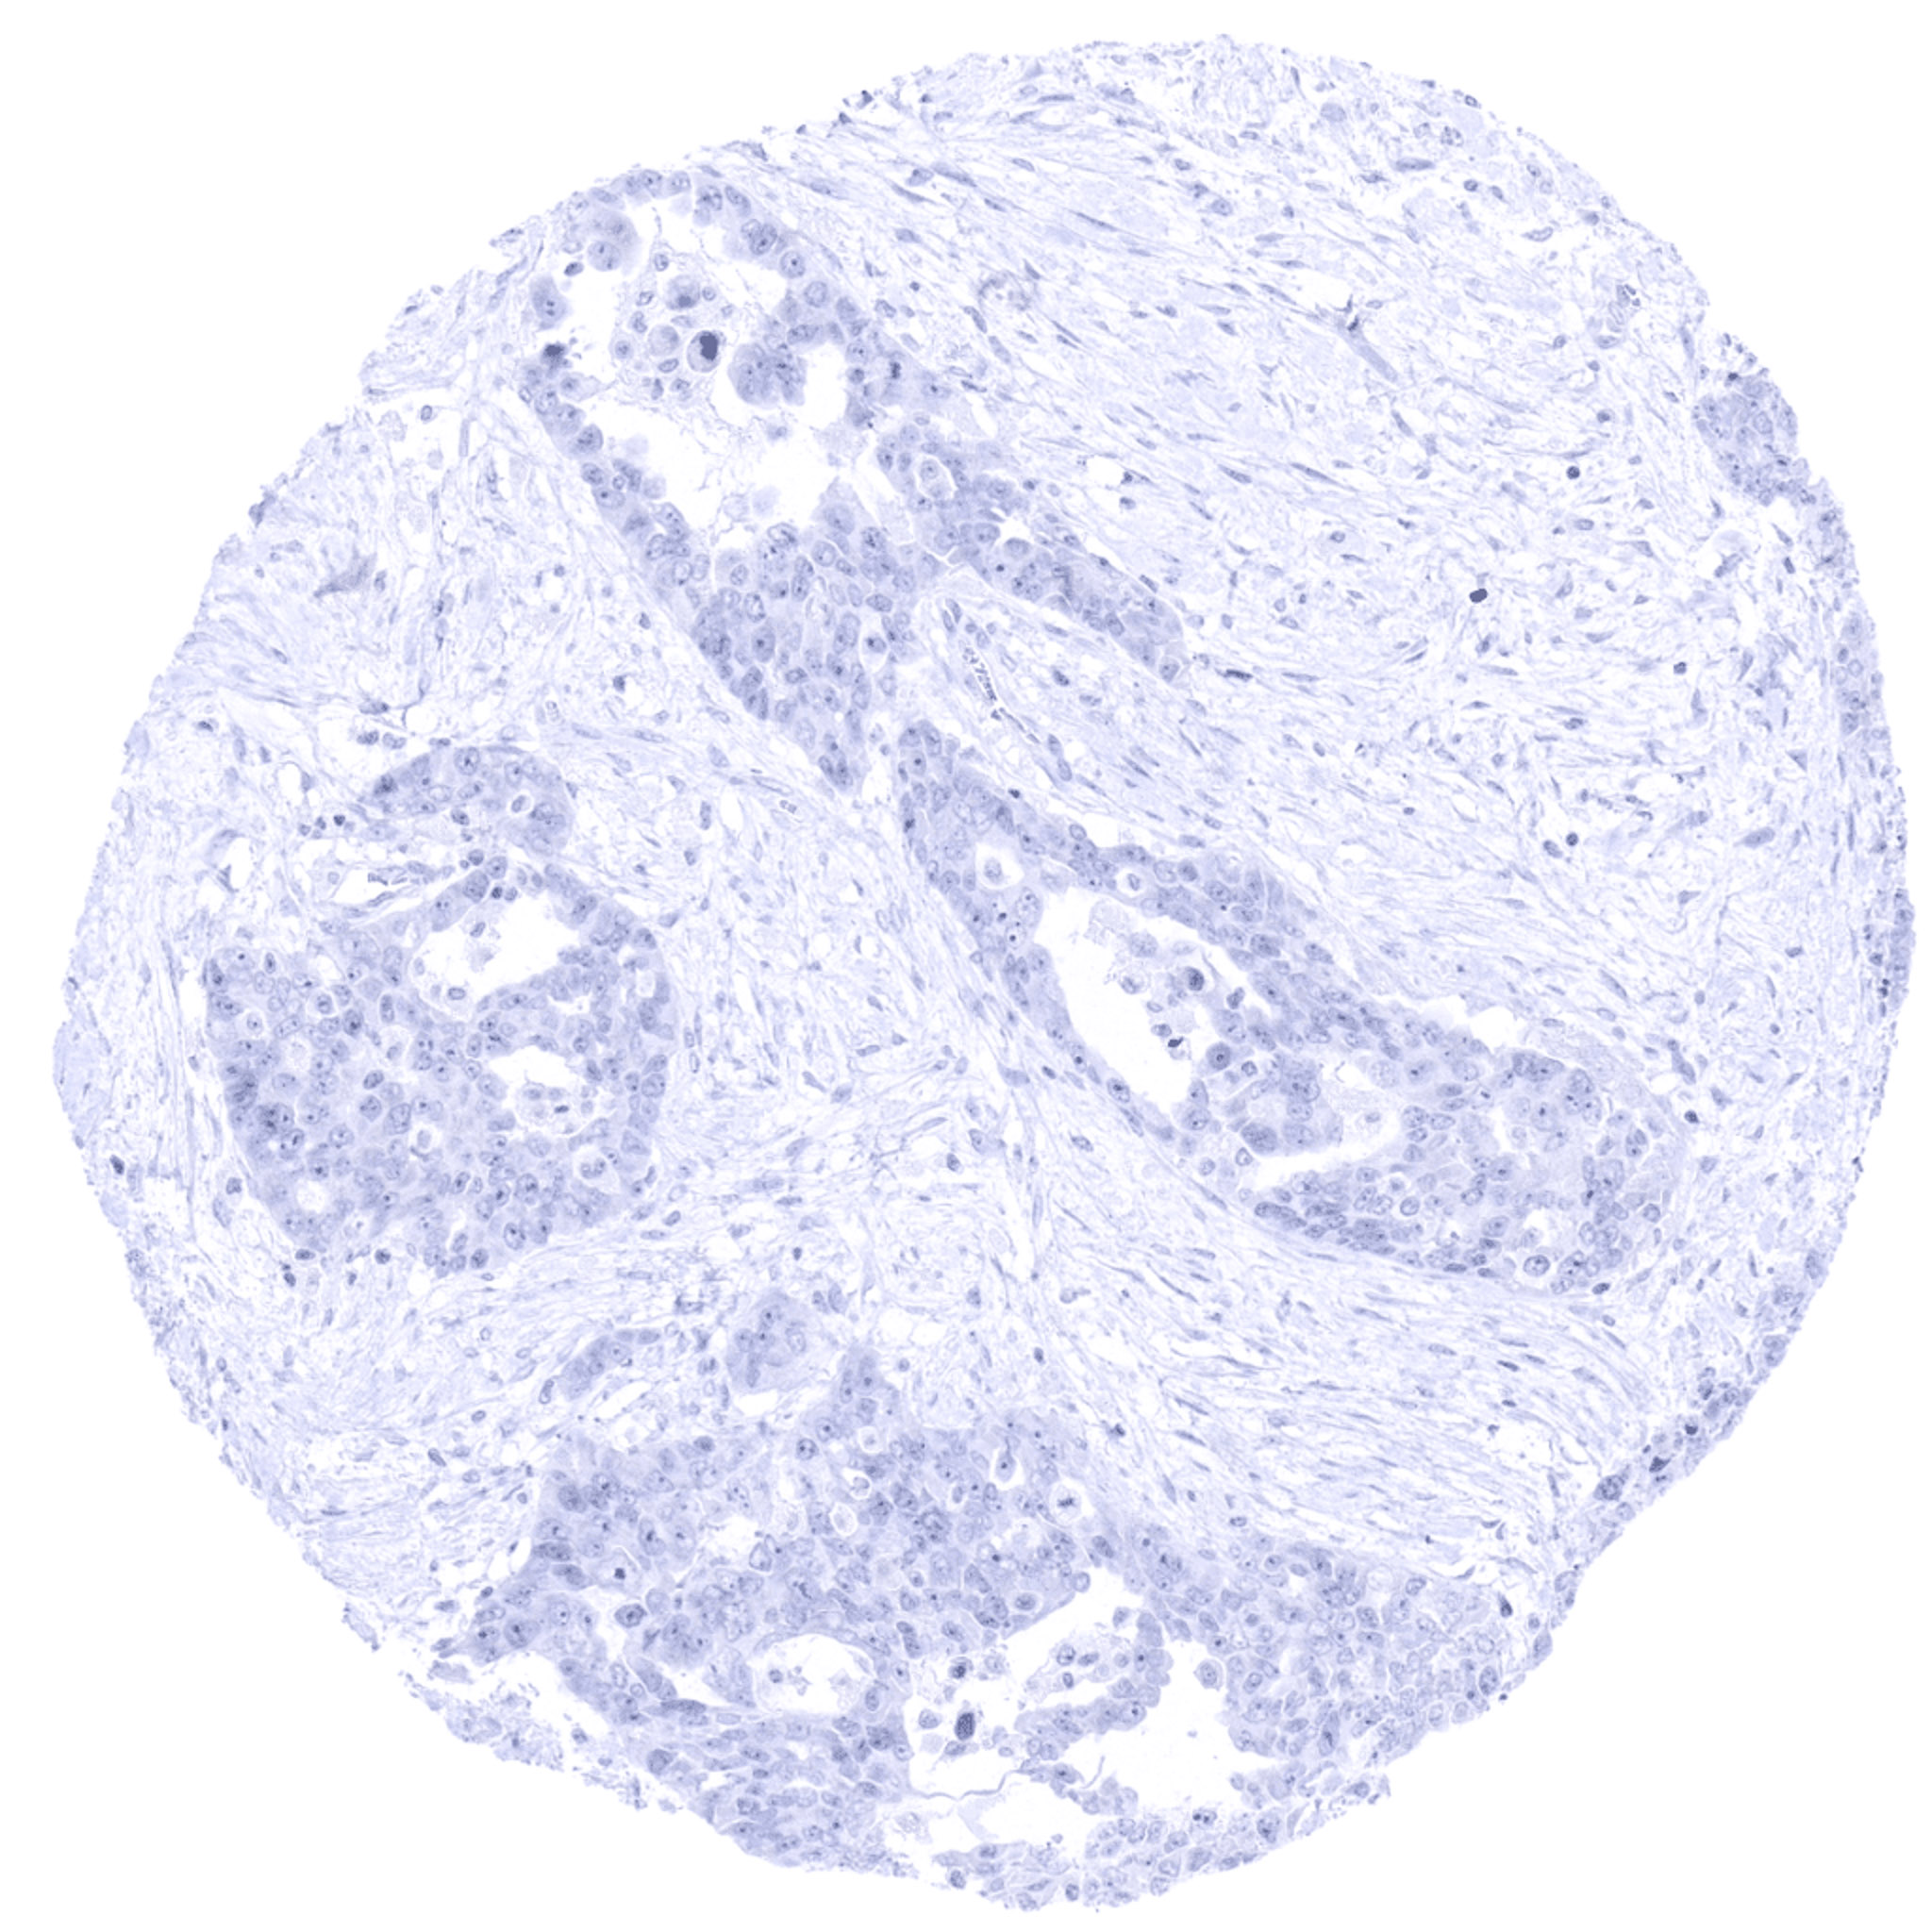

Urinary bladder- TdT negative muscle-invasive urothelial carcinoma.